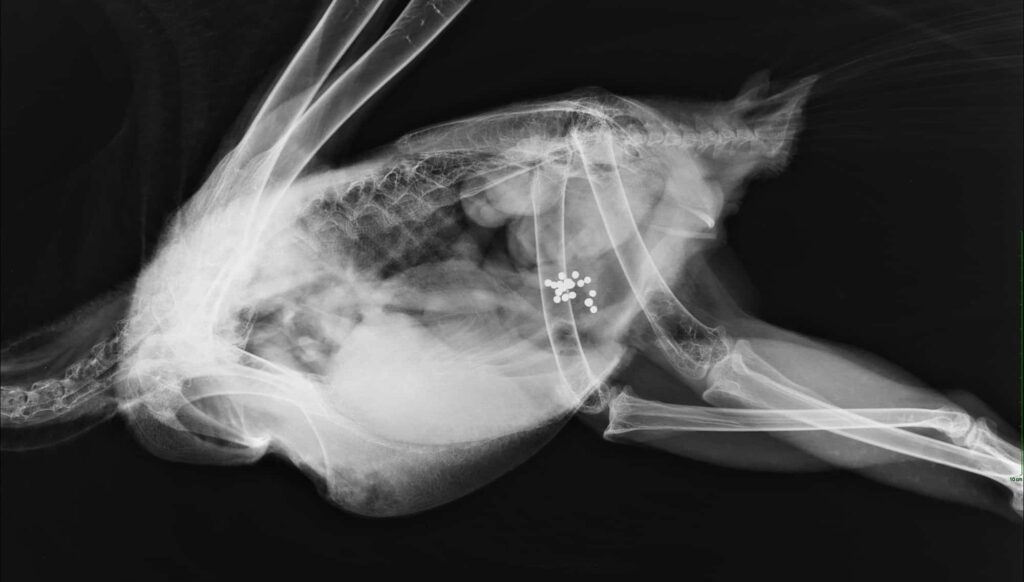

In the study published in Science, researchers—including scientists from the U.S. Geological Survey and the U.S. Fish and Wildlife Service—collected samples from 1,210 eagles in 38 states between 2010 and 2018. The samples showed what the authors described as “unexpectedly high frequencies” of both chronic and acute lead poisoning in both species. About 46% of both bald and golden eagles had chronic exposure.

Blood samples showed short-term, acute effects from recent poisoning. Liver and feather samples revealed slightly older exposures. Bone samples showed long-term effects of poisoning over a lifetime. Older eagles had higher contamination levels as the heavy metal accumulated in their bodies after multiple exposures.